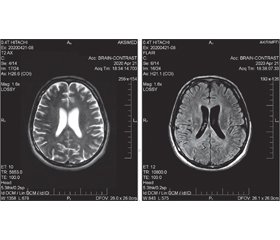

Під час дослідження ліквору визначаються лімфоцитарний плеоцитоз і ВІЛ. За показаннями проводяться електронейроміографія, електроенцефалографія (ЕЕГ), комп’ютерна томографія (магнітно-резонансна томографія (МРТ)) головного мозку, позитронно-емісійна комп’ютерна томографія.

На сагітальних зрізах МРТ головного мозку: ознаки дисциркуляторної енцефалопатії (церебральної мікроангіопатії — відповідно до шкали Fazekas 0–I). Відзначаються поодинокі МР-ознаки церебральної мікроангіопатії.